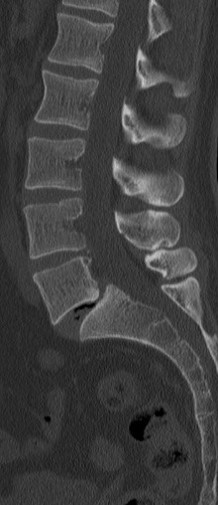

34 Yaşında Erkek Hasta

Low back pain

ODİ: %16

RM: 5/24

Ameliyat Öncesi